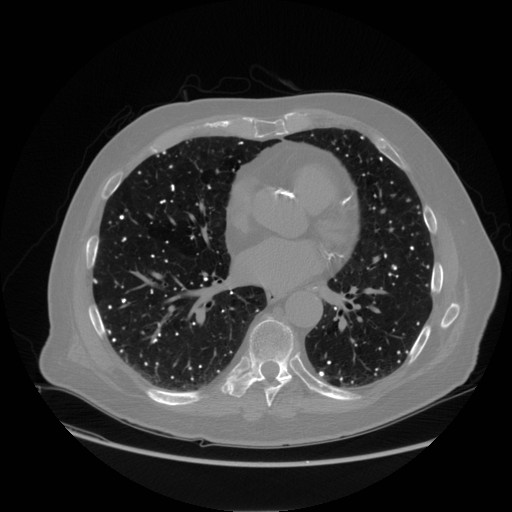

Gallery Pneumonia Varicella CT

Varicella CT